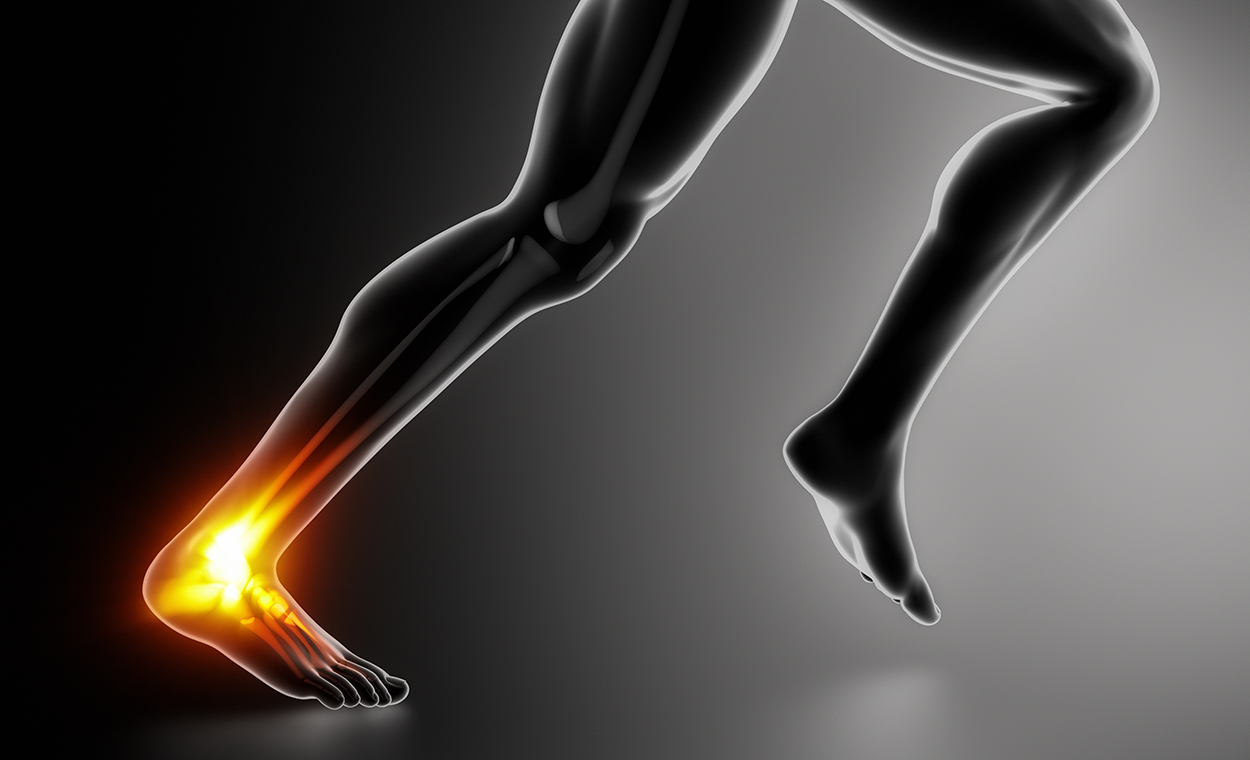

Achilles tendinopathy is a common condition, particularly in individuals who participate in running and jumping activities. The incidence is higher in individuals between 30-55 years of age.

Usually there will be a change in load (Volume, Speed, Intensity or Frequency). Aggravating activities will involve compression of the tendon by another structure, or from higher loads through the tendon (e.g. running, jumping). Tendon pain will usually “warm up with activity”. There may be morning stiffness, and symptoms can be worse for hours/days after activity.

Other structures that could be a source of symptoms include the Plantaris tendon, fat pad, paratendon, an accessory soleus, the flexor retinaculum, and retrocalcneal bursa.

- In cases of insertional Achilles tendinopathy, it is crucial to Avoid compression< of the tendon when the ankle is dorsiflexed. Stretching is not beneficial, and we can place heel wedges in your shoes to unload the tendon.